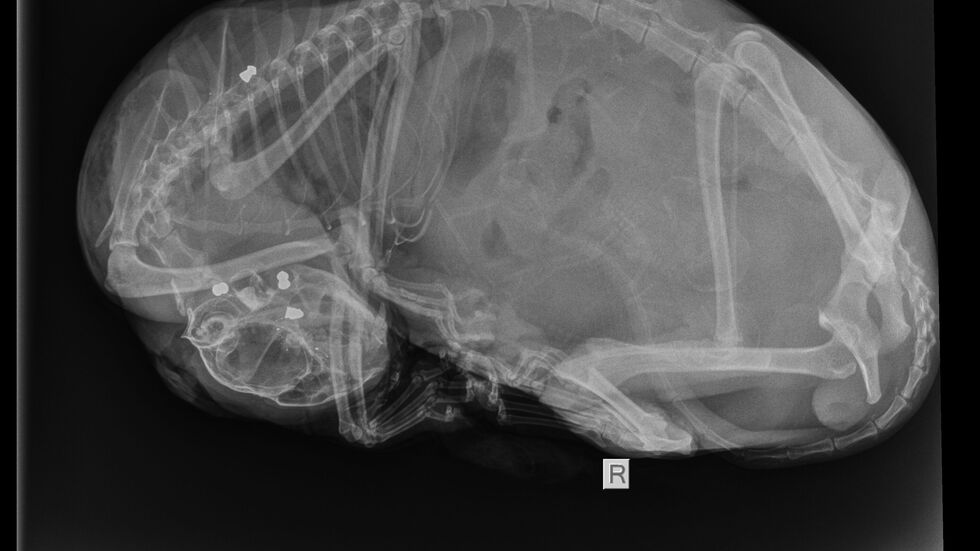

- Auf dem Röntgenbild sind insgesamt vier Projektile zu sehen, drei davon im Kopf der Katze.

Auf den Röntgenbildern wird deutlich, wie es dem Tier ergangen sein muss. „Drei Projektile steckten im Kopf der Katze. Das lässt den abartigen Schluss zu, dass sie fixiert gewesen sein muss und der Täter oder die Täterin dann auf sie geschossen hat“, sagte Tierheimchefin Claudia Ruf unserem Sender entsetzt. Ein viertes Projektil wurde in der Schulter der Katze gefunden.